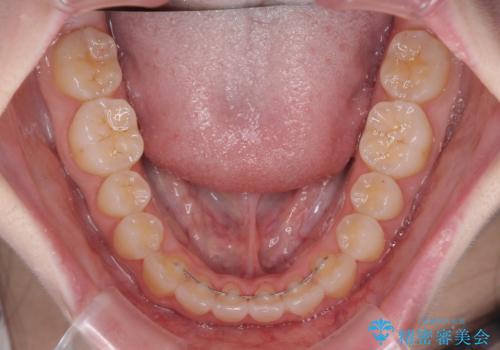

- 前歯の捻れと、ちょっとした出っ張りを気にして来院された患者様です。

歯と歯の間を削る(IPR)ことでデコボコを解消し、インビザラインで整えることとしました。

インビザライン治療特有の奥歯が接触しない時期が続き、当初予定よりも期間がかかりましたが、最終的には安定した咬み合わせと、整った前歯になりました。